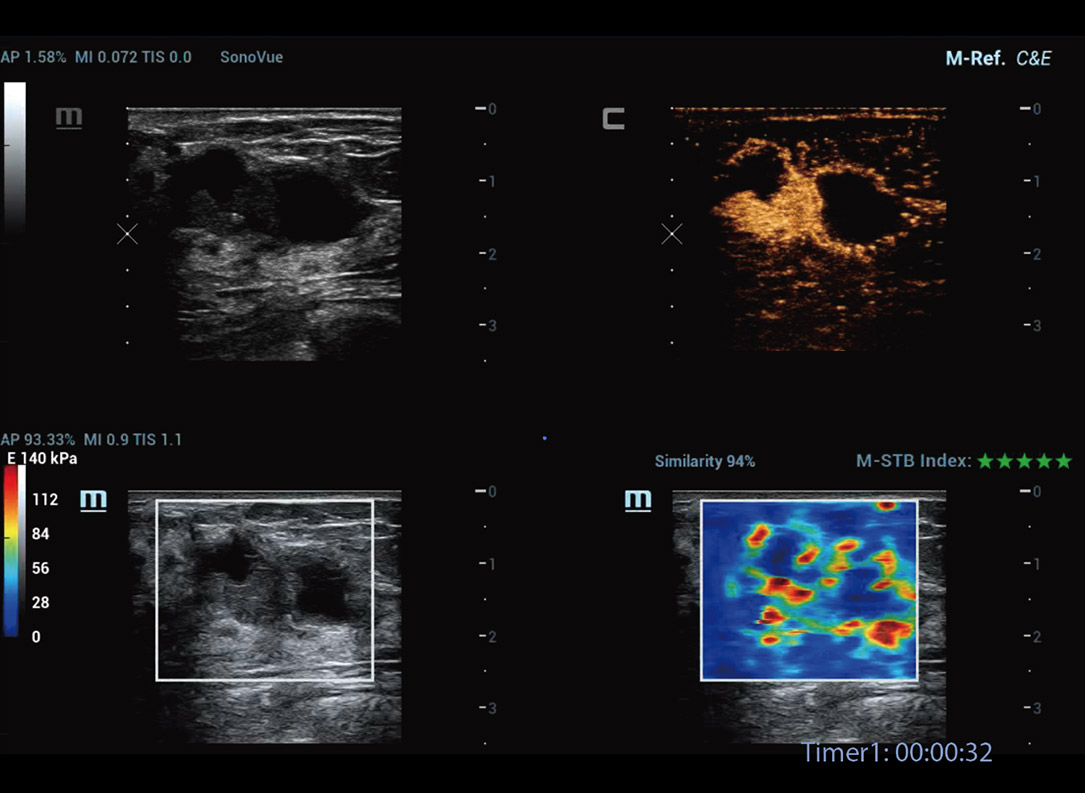

M-Reference C&E

CEUS en shear-wave ontrafelen samen de multi-parametrische echografiewereld

M-Reference Multi-parametrische analysetools

M-Ref. C&E

M-Ref. C&E Borst kwaadaardig

M-Ref. C&E ondersteunt het weergeven van het contrast en de STE in ├®├®n vlak voor vergelijkende beoordeling van perfusie en elasticiteit.

M-Ref. E Compare

M-Ref. E Compare Borst kwaadaardig

M-Ref. E Compare ondersteunt het weergeven van zowel de realtime strain-elastografie als STE in ├®├®n vlak voor de evaluatie van weefselstijfheid.

Geavanceerde CEUS

UWN+(Ultra-Wideband Niet-linear) CEUS

CEUS Borst kwaadaardig

Door gebruik te maken van zowel de 2e harmonische als niet-lineaire fundamentele signalen, maaktUWN+ een hoge gevoeligheid van bubbelsignalen en langere contrastperfusie met een lagere MI mogelijk, wat helpt bij tumorbeoordelingen.

Nieuwe CEUS-kwantificatieanalyse

Nieuwe CEUS QA Borst kwaadaardig

De tijd-intensiteitscurve maakt kwantitatieve analyse van CEUS-beeldvorming mogelijk. De nieuwe CEUS QA biedt tools voor geavanceerde kwantitatieve analyse die ondersteuning bieden bij tumorbeoordelingen en klinisch onderzoek.